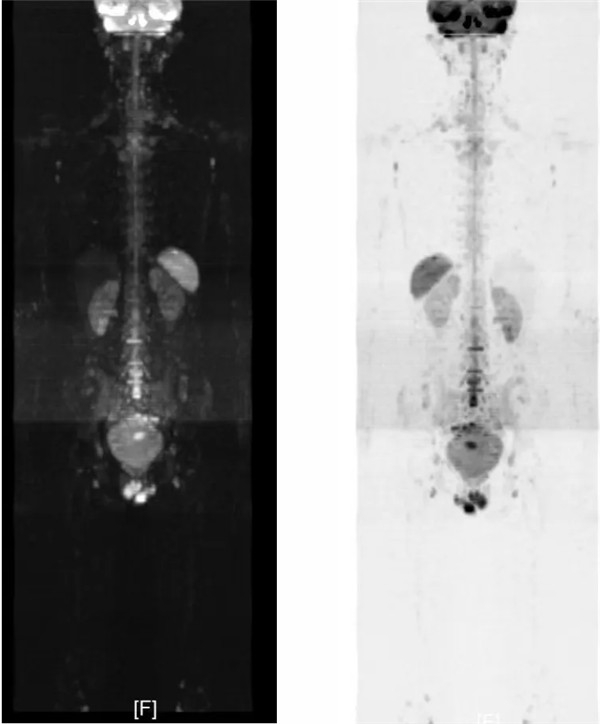

近日,血液腫瘤內科一位年輕霍奇金淋巴瘤患者,經近1年治療后獲得了完全緩解的最佳療效。定期復查在此類疾病中尤為重要,在此病例中,血液腫瘤內科與醫學影像科反復多次溝通討論,根據病情特點,為患者量身選取制定:全身核磁共振彌散成像(DWI)為優選復查方式,利用核磁共振(MRI)對水分子的彌散敏感特性,通過特殊設計的序列快速產生一系列全身MR圖像,清晰顯示人體內部結構和生理狀態,尤其是細胞級的病變,同時在成像過程中抑制了肌肉、脂肪、肝臟等組織背景信號,使得病變區域的顯示更加突出,提高了病變組織的檢出率,精準地區分良惡性病變。最終為患者準確評估了疾病狀態。全身DWI在腫瘤診斷中有:無創無害、一次完成全身掃描、高敏感性和特異性、多功能成像等多重優勢,為醫生診斷治療提供了更全面的信息。